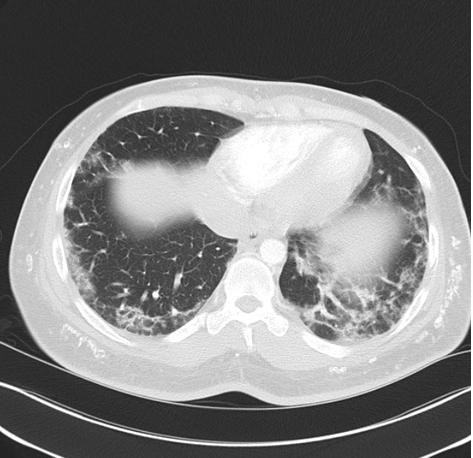

皮肌炎和多发性肌炎患者的肺部并发症很常见,也是炎症肌病患者的重要死因之一。常见的临床表现为呼吸困难、咳嗽。采用敏感性高的高分辨率CT、肺功能检查可在70%的患者发现肺部病变。

除呼吸肌无力外,肺部组织炎症也是重要原因。炎性肌病损伤肺部组织时表现为间质性肺疾病(interstitial lung disease, ILD)。根据肺部受累的病理可以分为:

患者的间质性肺疾病的出现时机不定。可以在皮疹、肌肉症状出现前,也可以同时或此后出现。少数人存在快速进展的肺部病变,例如急性间质性肺炎带来弥漫性肺泡损伤。但大多数患者表现轻微、进展缓慢。

每个拟诊皮肌炎或多发性肌炎的患者都应行高分辨率CT检查肺部。尽管肺间质病变患者可在吸气后期听到固定的音调偏高水泡音----velcro啰音。但并非所有肺间质病变都存在。单纯以肺部听诊正常就排除掉肺间质病变是错误的。

皮肌炎的胸部CT表现